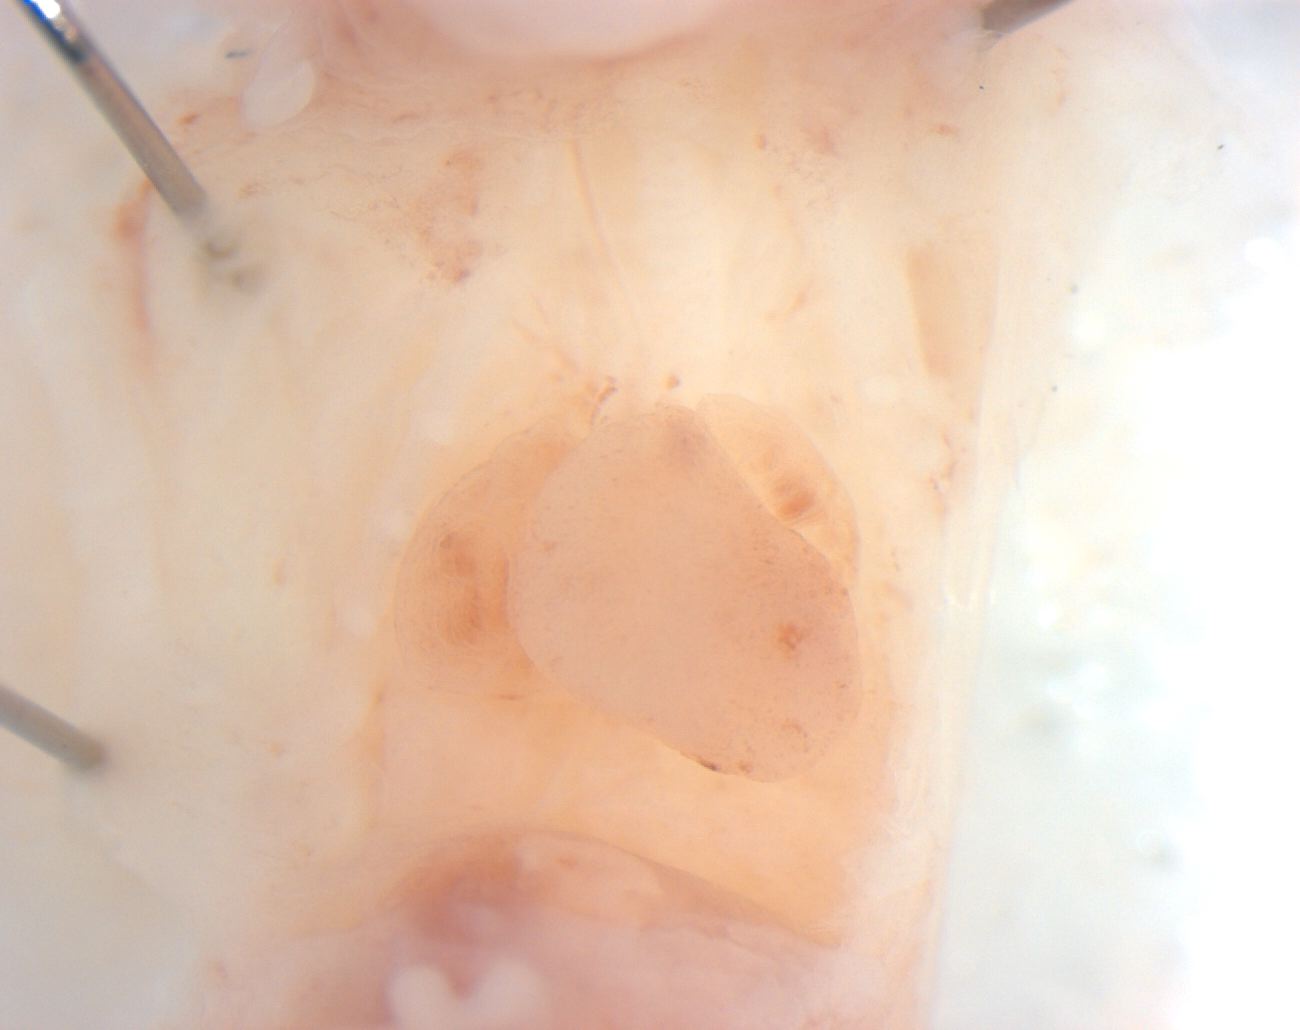

Caption Mutant 2025-007-1 (E16.5) exhibits an abnormal patterning on the ventricles which is diagnosed as ventricular non-compaction by EFIC imaging